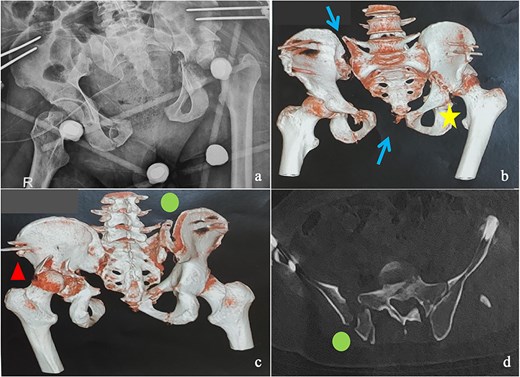

This was a 42-year-old male patient with no previous medical history who was admitted to the intensive care unit for treatment of polytrauma: severe chest trauma and pelvic trauma. During his stay in intensive care, the patient developed a pulmonary infection complicated by septicemia, requiring prolonged antibiotic therapy and thereby contraindicating any internal surgical fixation. After hemodynamic and respiratory stabilization, he was transferred to our department 40 days after the trauma with the following injuries: an unstable pelvic ring fracture classified as Tile-AO B1-2 [4]: disjunction of the pubic symphysis, disjunction of the right sacroiliac joint, and an ipsilateral crescent fracture classified as Kumar-Day 2 [5], along with a transverse–posterior wall fracture of the left acetabulum associated with a posterior dislocation of the hip, which was initially reduced but remained unstable. Fixation was performed using a Hoffmann II external fixator applied to the iliac crests with poor reduction (Fig. 1). He presented with complete weakness of the left foot dorsiflexors, with preserved sensation and no urogenital or abdominal complications. ORIF was performed in two stages, 5 days apart. The first stage consisted of performing the first two windows of the ilioinguinal approach: the lateral window to access the sacroiliac joint and the middle window to access the lower part of the sacroiliac joint and remove the osteofibrous callus. A Pfannenstiel approach was used to remove the callus at the pubic symphysis and fix it with a plate. The patient was then placed in the prone position and a posterior approach to the right sacroiliac joint was performed to carry out the same procedures on the posterior part of this joint and to perform fixation using ilioiliac and iliosacral screws. The second stage of the operation involved acetabular surgery. Given the chronic dislocation of the left hip, an anterior approach to the hip was performed to remove the intra-articular fibrosis facilitating the subsequent reduction of the femoral head. A Kocher-Langenbeck approach was then performed to remove the callus, reduce the femoral head and fracture, and fix it with a plate (Fig. 2). Postoperatively, the patient retained neurological deficits. At 6 months, the patient was able to walk without assistance and had a Harris Hip Score (HHS) score of 80 and Majeed score of 75 [6, 7].

(a) Anteroposterior pelvic X-ray showing delayed pelvic and acetabular fractures. (b) Anterior view of the pelvis on 3D section: pubic symphysis disjunction and right sacroiliac dislocation (arrows), transverse component of the left acetabular fracture (star). (c) Posterior view of the pelvis on 3D section: right crescent fracture associated with right sacroiliac dislocation (circles), fracture of the posterior wall of the left acetabulum associated with posterior dislocation of the femoral head (triangle). (d) Axial section of the pelvic CT-scan: right crescent fracture Kumar-Day 2 (green arrow).